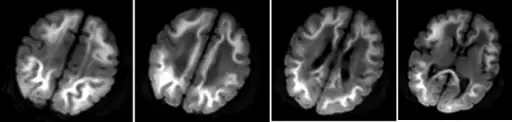

Infant with methylmalonic acidemia- diffusion restriction in subcortical white matter of bilateral cerebral hemispheres

Because of the inability to properly break down amino acids completely, the byproduct of protein digestion, the compound methylmalonic acid, is found in a disproportionate concentration in the blood and urine of those afflicted. These abnormal levels are used as the main diagnostic criteria for diagnosing the disorder. This disorder is typically determined through the use of a urine analysis or blood panel.[14] The presence of methylmalonic acidemia can also be suspected through the use of a CT or MRI scan or ammonia test, however these tests are by no means specific and require clinical and metabolic/correlation.[4] Elevated levels of ammonia, glycine, and ketone bodies may also be present in the blood and urine.[7]